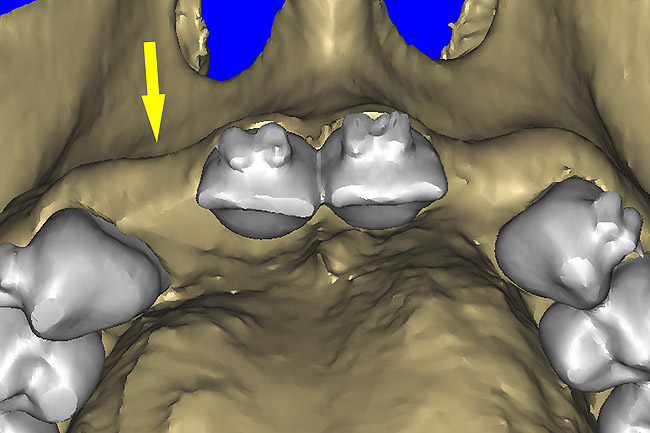

Using different masking (segmentation) and threshold Hounsfield unit values, several new 3D bone volumes can be created which offer invaluable information. To help determine the final position of each implant a new bone model was created with a Hounsfield unit value of 1480, which eliminated all but the densest objects included in the scan data. (Results may vary depending on the CBCT machine used.) The inner and outer layers of bone were removed, leaving the underlying enamel and root structure of the teeth (Figure 8A). After the bone had been stripped away, the root inclinations were examined closely. The most striking findings confirmed the rotated position of the right central, while revealing the slight mesial dilaceration of the root apex, which converged on the space needed for the path of the potential implant (Figure 8B). The schematic shapes of the proposed implants were visualized for the right and left lateral spaces in different rotations of the 3D maxillary arch. It was at this point that a determination was made as to the appropriate implant shape and type that would fit the available space while avoiding encroachment on adjacent tooth roots. A tapered design implant (Tapered Screw-Vent®, Zimmer Dental, www.zimmerdental.com) was chosen from the large virtual library. With the SIMPlant software, the virtual library contains data from dozens of implant manufacturers and realistic.computer-aided design representations as seen in Figure 9A through the translucent bone. The position of the left implant can be visualized with adequate mesial-distal distance between adjacent tooth roots (Figure 9B) and a more delicate placement (Figure 9C).

Figure 12a  (A) By sectioning the 3D model, virtual implant placement was assessed for the necessary 2 mm of facial and palatal bone surrounding the implant, and (B) by using segmentation techniques to remove the existing teeth, leaving the sockets, the alveolar complex was appreciated fully.

Figure 12a

Figure 12b  (A) By sectioning the 3D model, virtual implant placement was assessed for the necessary 2 mm of facial and palatal bone surrounding the implant, and (B) by using segmentation techniques to remove the existing teeth, leaving the sockets, the alveolar complex was appreciated fully.

Figure 12b